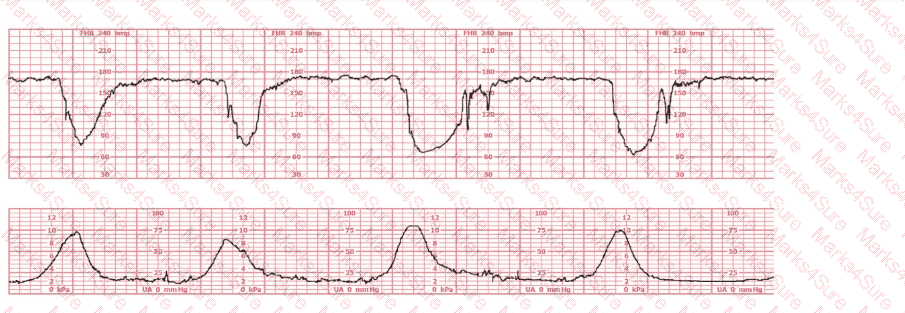

A woman at 38-weeks gestation is admitted to labor and delivery following a fall down the stairs three hours ago. She started feeling contractions in the ambulance. The fetal heart rate tracing shown is on initial evaluation and represents 25 minutes. This tracing is most consistent with a